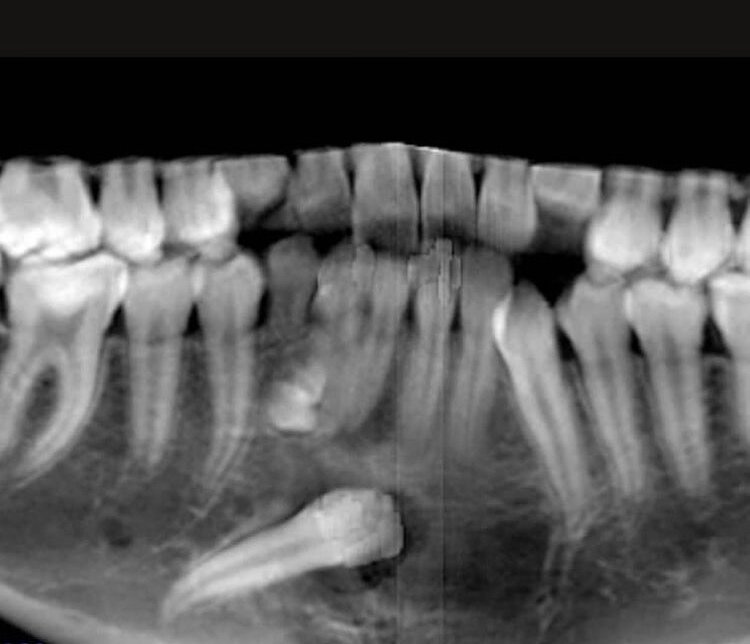

На фото кейс с клыком, который лежал в подбородке. Его «растили» наши доктора Дудина Ольга Александровна и Федосов Александр Викторович.

Ортодонт в данном случае без хирурга никуда! Коллегиальность, синхронность, немного удачи и доверие пациента обязательно приводят к успеху!